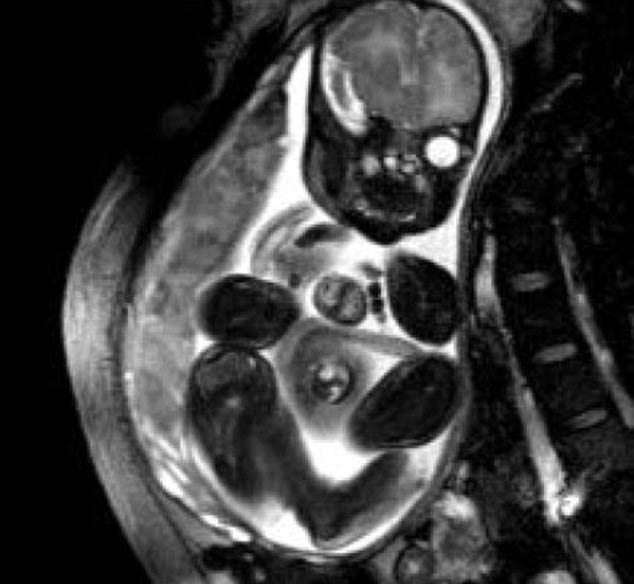

Sekiz milyonda bir meydana gelebilen bir hastalıkla doğan Audrina Cardenas bebek hayata tutundu.

Houston'da bulunan Texas Children 's Hospital'da geçirdiği başarılı ameliyatın ardından dünyaya yeniden gelen bebeğin sağlık durumu her geçen gün daha iyiye gidiyor.

MUCİZE BEBEĞİN KALBİ BÖYLE ATIYORDU - VİDEO